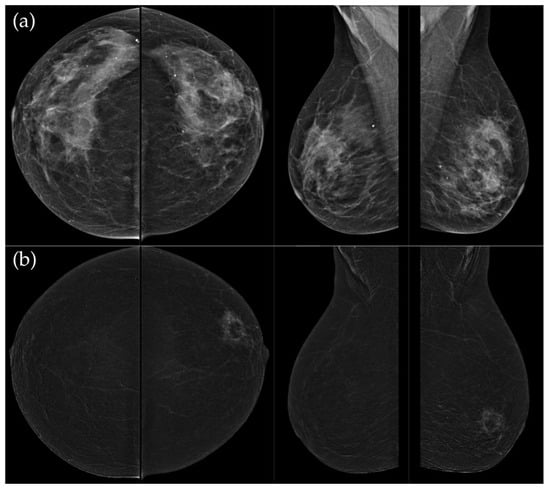

Figure 6. (a) Standard CC and MLO images reveal a relatively well-circumscribed, round to oval mass in the left retroareolar region, without suspicious calcifications. The right breast appears unremarkable. (b) On recombined contrast-enhanced images (CC and MLO), the same lesion demonstrates rim enhancement with irregular, heterogeneous internal contrast uptake. The enhancement shows early rapid contrast accumulation—a pattern that raises concern for malignancy. In the visualized portions of both axillae, no pathologically enhancing lymph nodes are identified. Histopathological examination confirmed the diagnosis of triple-negative breast carcinoma.